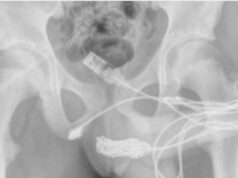

Un chico intentaba medir su pene y se le enredó un cable USB en...

La familia llevó al menor al hospital cuando éste comenzó a orinar sangre. Después de que los intentos iniciales de quitar el cable no...